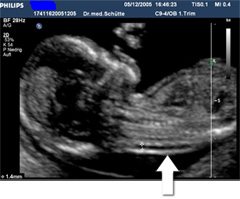

Messung der Nackentransparenz

Dieses Bild zeigt eine unauffällige

Nackentransparenz.